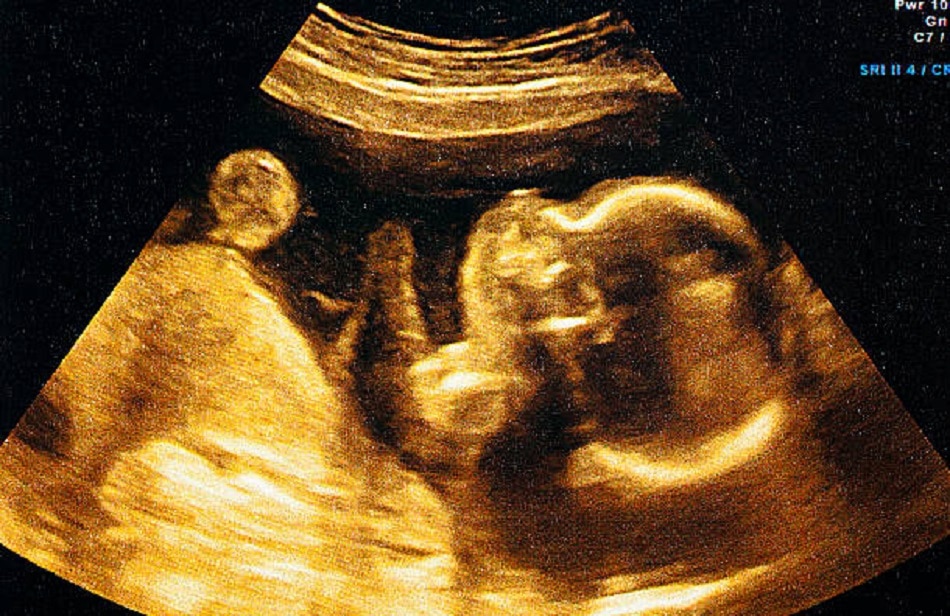

अब सवाल उठता है कि जब फर्टिलाइजेशन का तरीका वही है तो ये कैसे तय होता है कि भ्रूण लड़के में तब्दील होगा या लड़की में? आमतौर पर किसी महिला को एक महीने बाद प्रेग्नेंसी का अहसास होता है. तब तक शरीर में भ्रूण बन चुका होता है जिसका आकार 6 मिलीमीटर यानी मटर के दाने से भी आधा होता है. इस वक्त तक भ्रूण की गर्दन और हाथ-पैर बनना शुरू हो जाते हैं.

9वें हफ्ते के आस-पास लिंग बनना शुरू हो जाता है. इस वक्त तक इसे अल्ट्रासाउंड के जरिए नहीं देखा जा सकता है. ऐसा भी हो सकता है कि रीप्रोडक्टिव ग्लैंड्स ओवेरीज़ में तब्दील होने लगे. ऐसे में एस्ट्राडियॉल नाम का हार्मोन रिलीज होने लगता है. जिन देशों में भ्रूण के लिंग जांचने की इजाजत है, वहां डॉक्टर 12वें से 14वें हफ्ते के बीच इस बारे में कुछ बता पाते हैं.